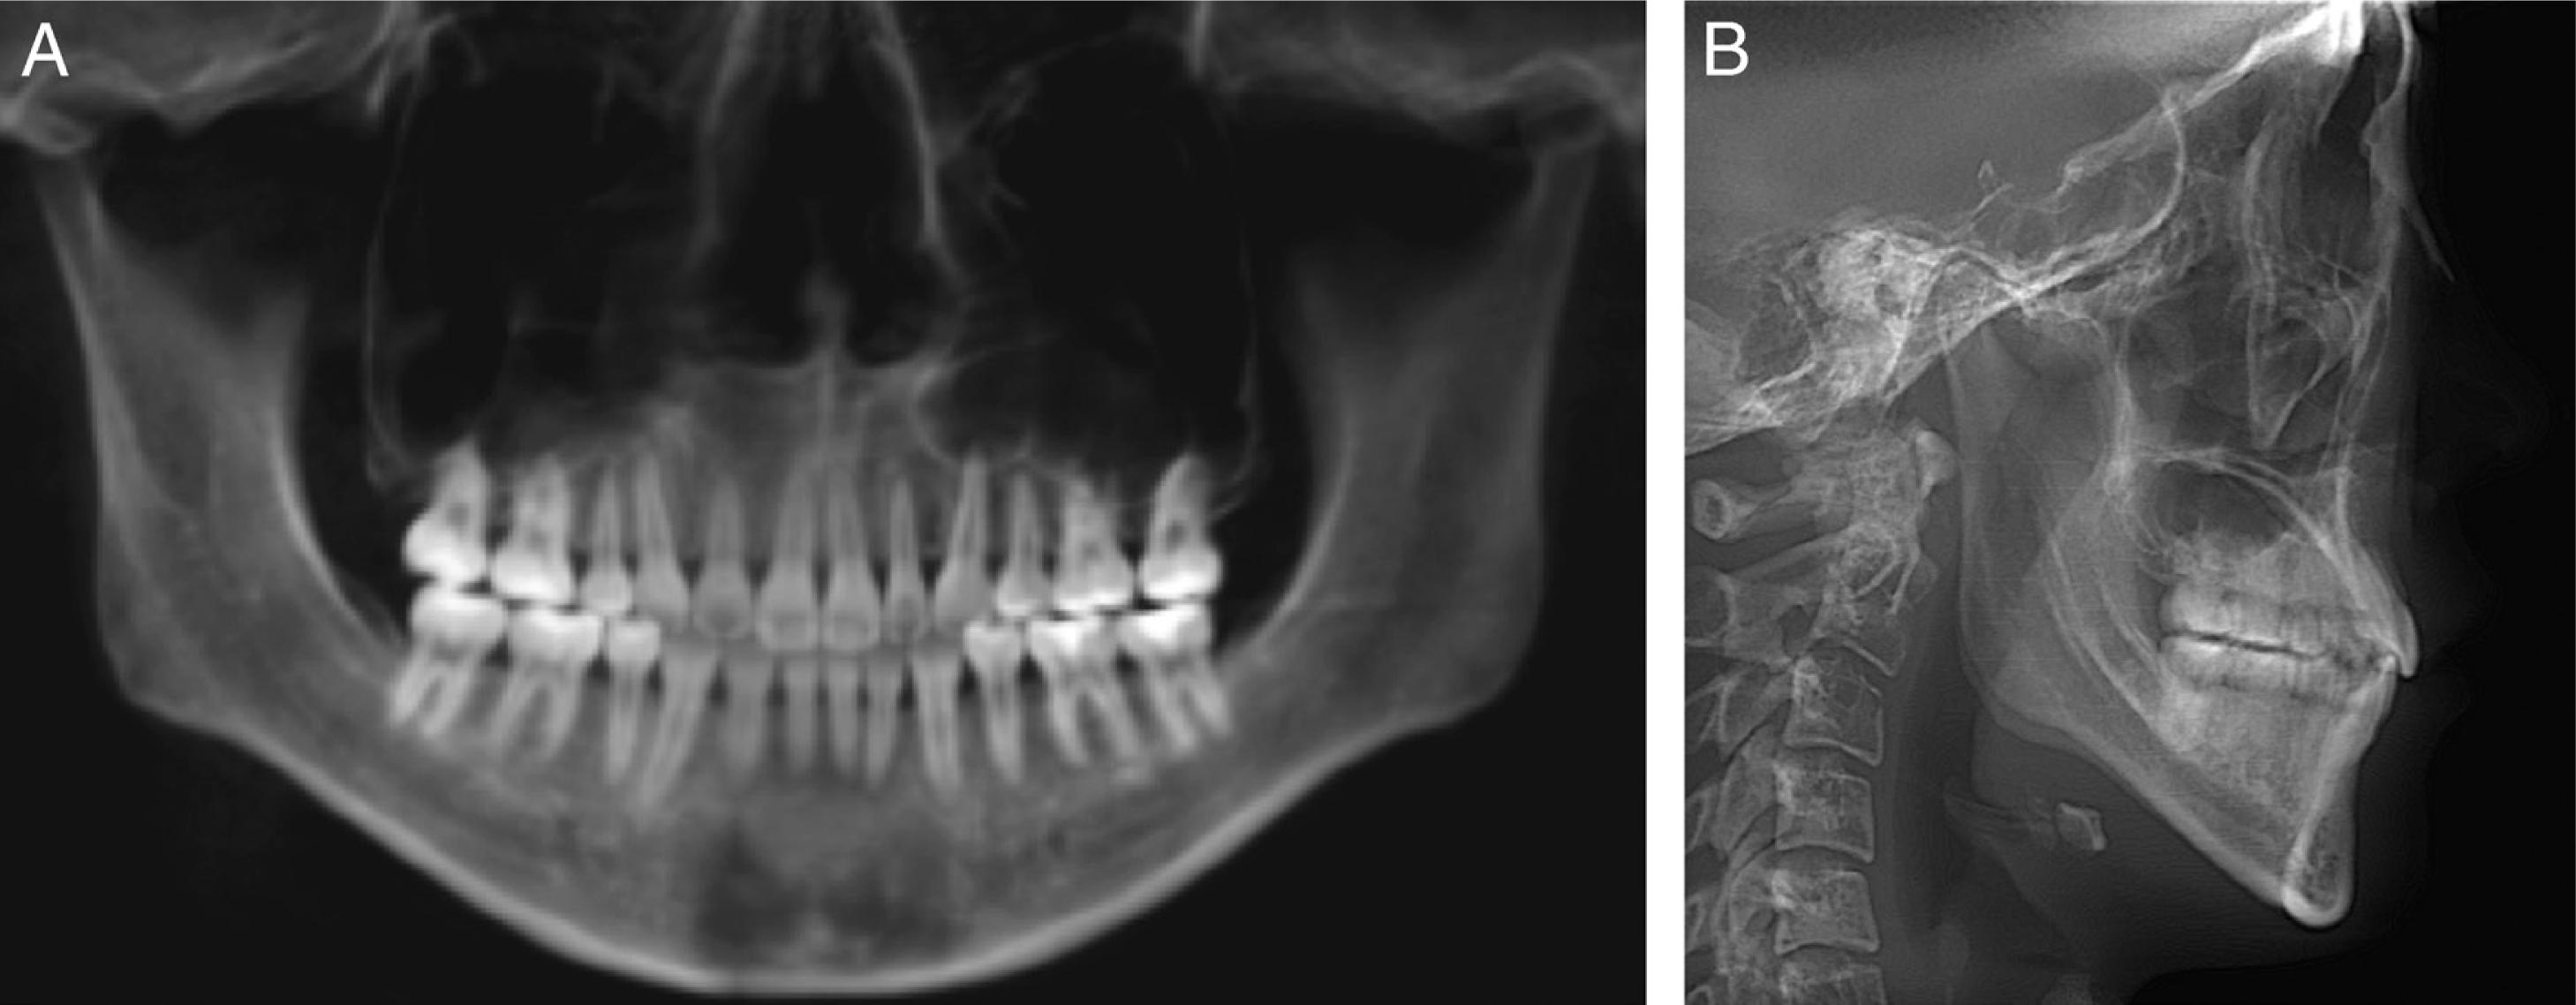

A 24-year-old female patient presented with a history of tongue thrust and mouth breathing but without a history of maxillofacial trauma or a non-nutritive sucking habit. The diagnostic records revealed that, based on the E line, the patient had a convex profile with a long face, a decreased nasolabial angle, a protrusive lower lip, and a shallow mentolabial sulcus. Further, the patient had incompetent and protruded lips at rest and in contact but with mentalis strain upon forcible closure. There was also a low smile line, and the smile arc was not consonant with the curvature of the lower lip (Figure 1). An intraoral examination showed an anterior open bite with no occlusal contact from the right first premolar to the left first premolar, a bilateral Class III molar relationship, and a Class III canine relationship on the right side but a Class I relationship on the left side. An analysis of the initial study models revealed that there was an anterior dental open bite of 6 mm, a decreased overjet (the overjet and overbite were measured on digital dental models using 3-shape software), a 3 mm curve of Spee, a mandibular midline deviation (1.5 mm to the left), and arch-length discrepancies of 5 mm in the maxilla and 3 mm in the mandible. The anterior and overall Bolton ratios were compatible. The maxillary dental arch was narrow, and the upper and lower arches were unmatched. A crossbite from the upper left canine to the second premolar was also noted during the examination. The maxillary right second molar was in scissor-bite with the mandibular right second molar (Figure 2). A cephalometric analysis revealed a skeletal open bite (SN/GO-GN 48°), an increased mandibular plane angle, a counter-clockwise rotation of the ANS-PNS plane (S-N/ANS-PNS 6°), proclination of the upper incisors (UI/ANS-PNS 129°), an interincisal angle of 108°, excessive lower anterior facial height and a short upper anterior facial height (Table I). A computed tomography scan of the anterior teeth revealed adequate labial and lingual bone volumes (Figure 3A). In addition, the initial panoramic radiograph and the radiographic and clinical examinations of the temporomandibular joints revealed no obvious abnormalities (Figure 4 and 3B). The patient was diagnosed with a Class III malocclusion (S-N/ANS-PNS 6°) and skeletal open bite (SN/GO-GN 48°) with an increased mandibular plane angle, a long face, a convex profile, and lip incompetence with mentalis strain. There was also proclination of the upper incisors, a crossbite, scissor-bite, mild crowding and midline deviation.

Pre-treatment panoramic radiograph (A) and lateral cephalometric radiograph (B).